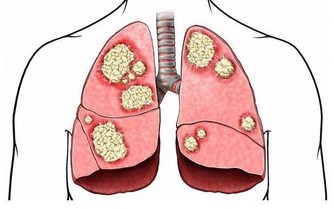

(三)胸腹部青筋

1.胸腹部青筋,多注意乳腺增生,經行乳房,脹痛,情志抑鬱。

2.腹部青筋,俗話說;“青筋過肚”。這已經是比較嚴重的積滯;成人肝硬化腹水,腫瘤後期。腹部青筋往往是比較難治的疾病。